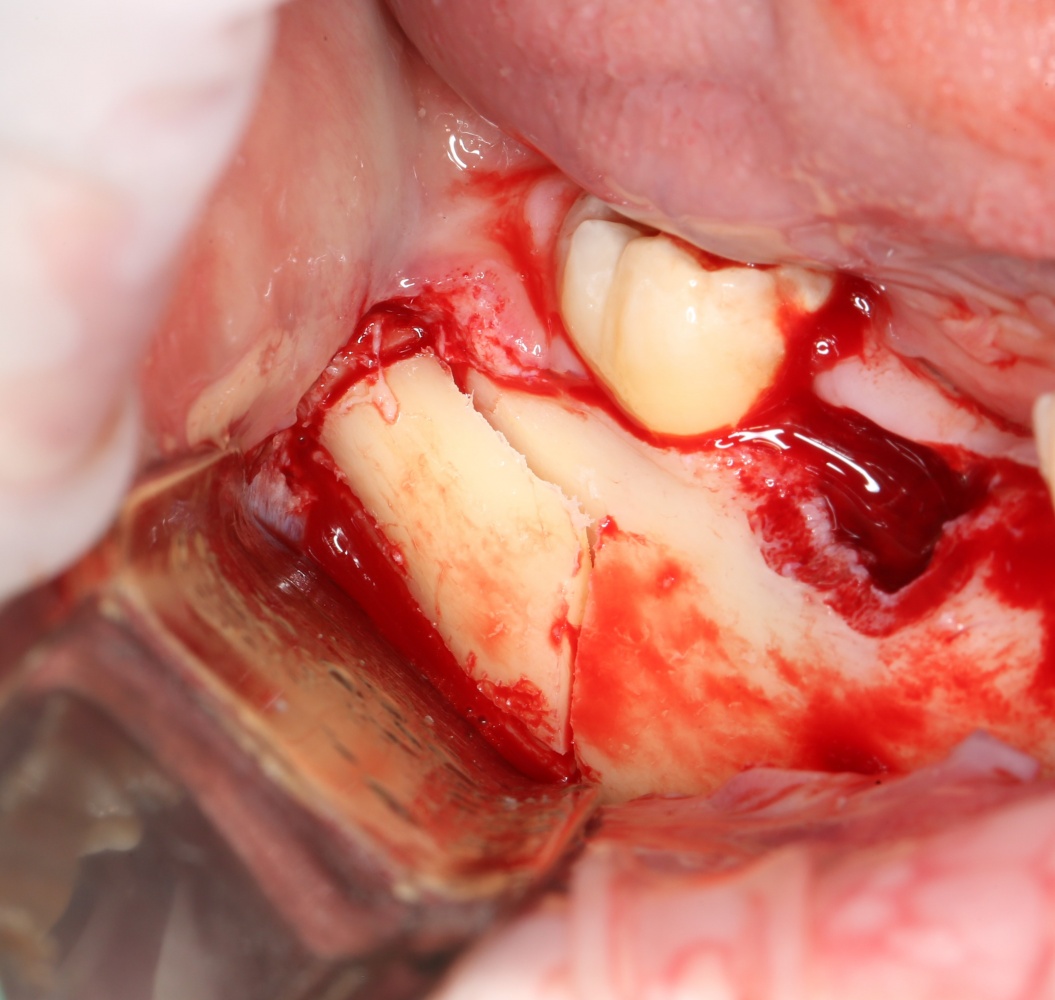

Простой. Надежный. Дешевый. Способ остеопластики.